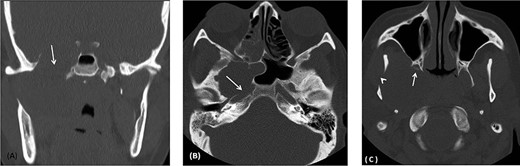

(A) Coronal CT image using bone window shows remodeling and widening of the oval foramen (arrow) secondary to infratemporal/middle cranial fossa mass. (B) axial CT images using bone window at the level of oval window demonstrates the widening of the canal with extension medially resulting in dehiscence of the anterior wall of the carotid canal (arrow). (C) Axial CT image using bone window at the infratemporal fossa level shows erosion and remodeling of the right pterygoid plates (Arrow) as well as the right mandible (arrowhead).

Computed tomography (CT) scan shows remodeling and widening of the right foramen ovale (Fig. 2A). This is associated with focal dehiscence at the right lateral wall of the sphenoid sinus and the anterior wall of the right carotid canal (Fig. 2B). The lesion extends downwards to the infratemporal fossa with remodeling of the pterygoid plates (Fig. 2C) and the right mandibular ramus.